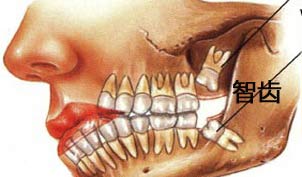

智齿是指人类口腔内,牙槽骨上里面的上下左右各一的四颗第三磨牙,是口腔靠近喉咙近的牙齿,通常是在人类心智已经趋于成熟时才长出,因而得名。智齿的位置从门牙牙缝开始,由一侧门牙向里数牙齿数目,如果有第八颗牙,它就是智齿。

智齿生长位置示意图